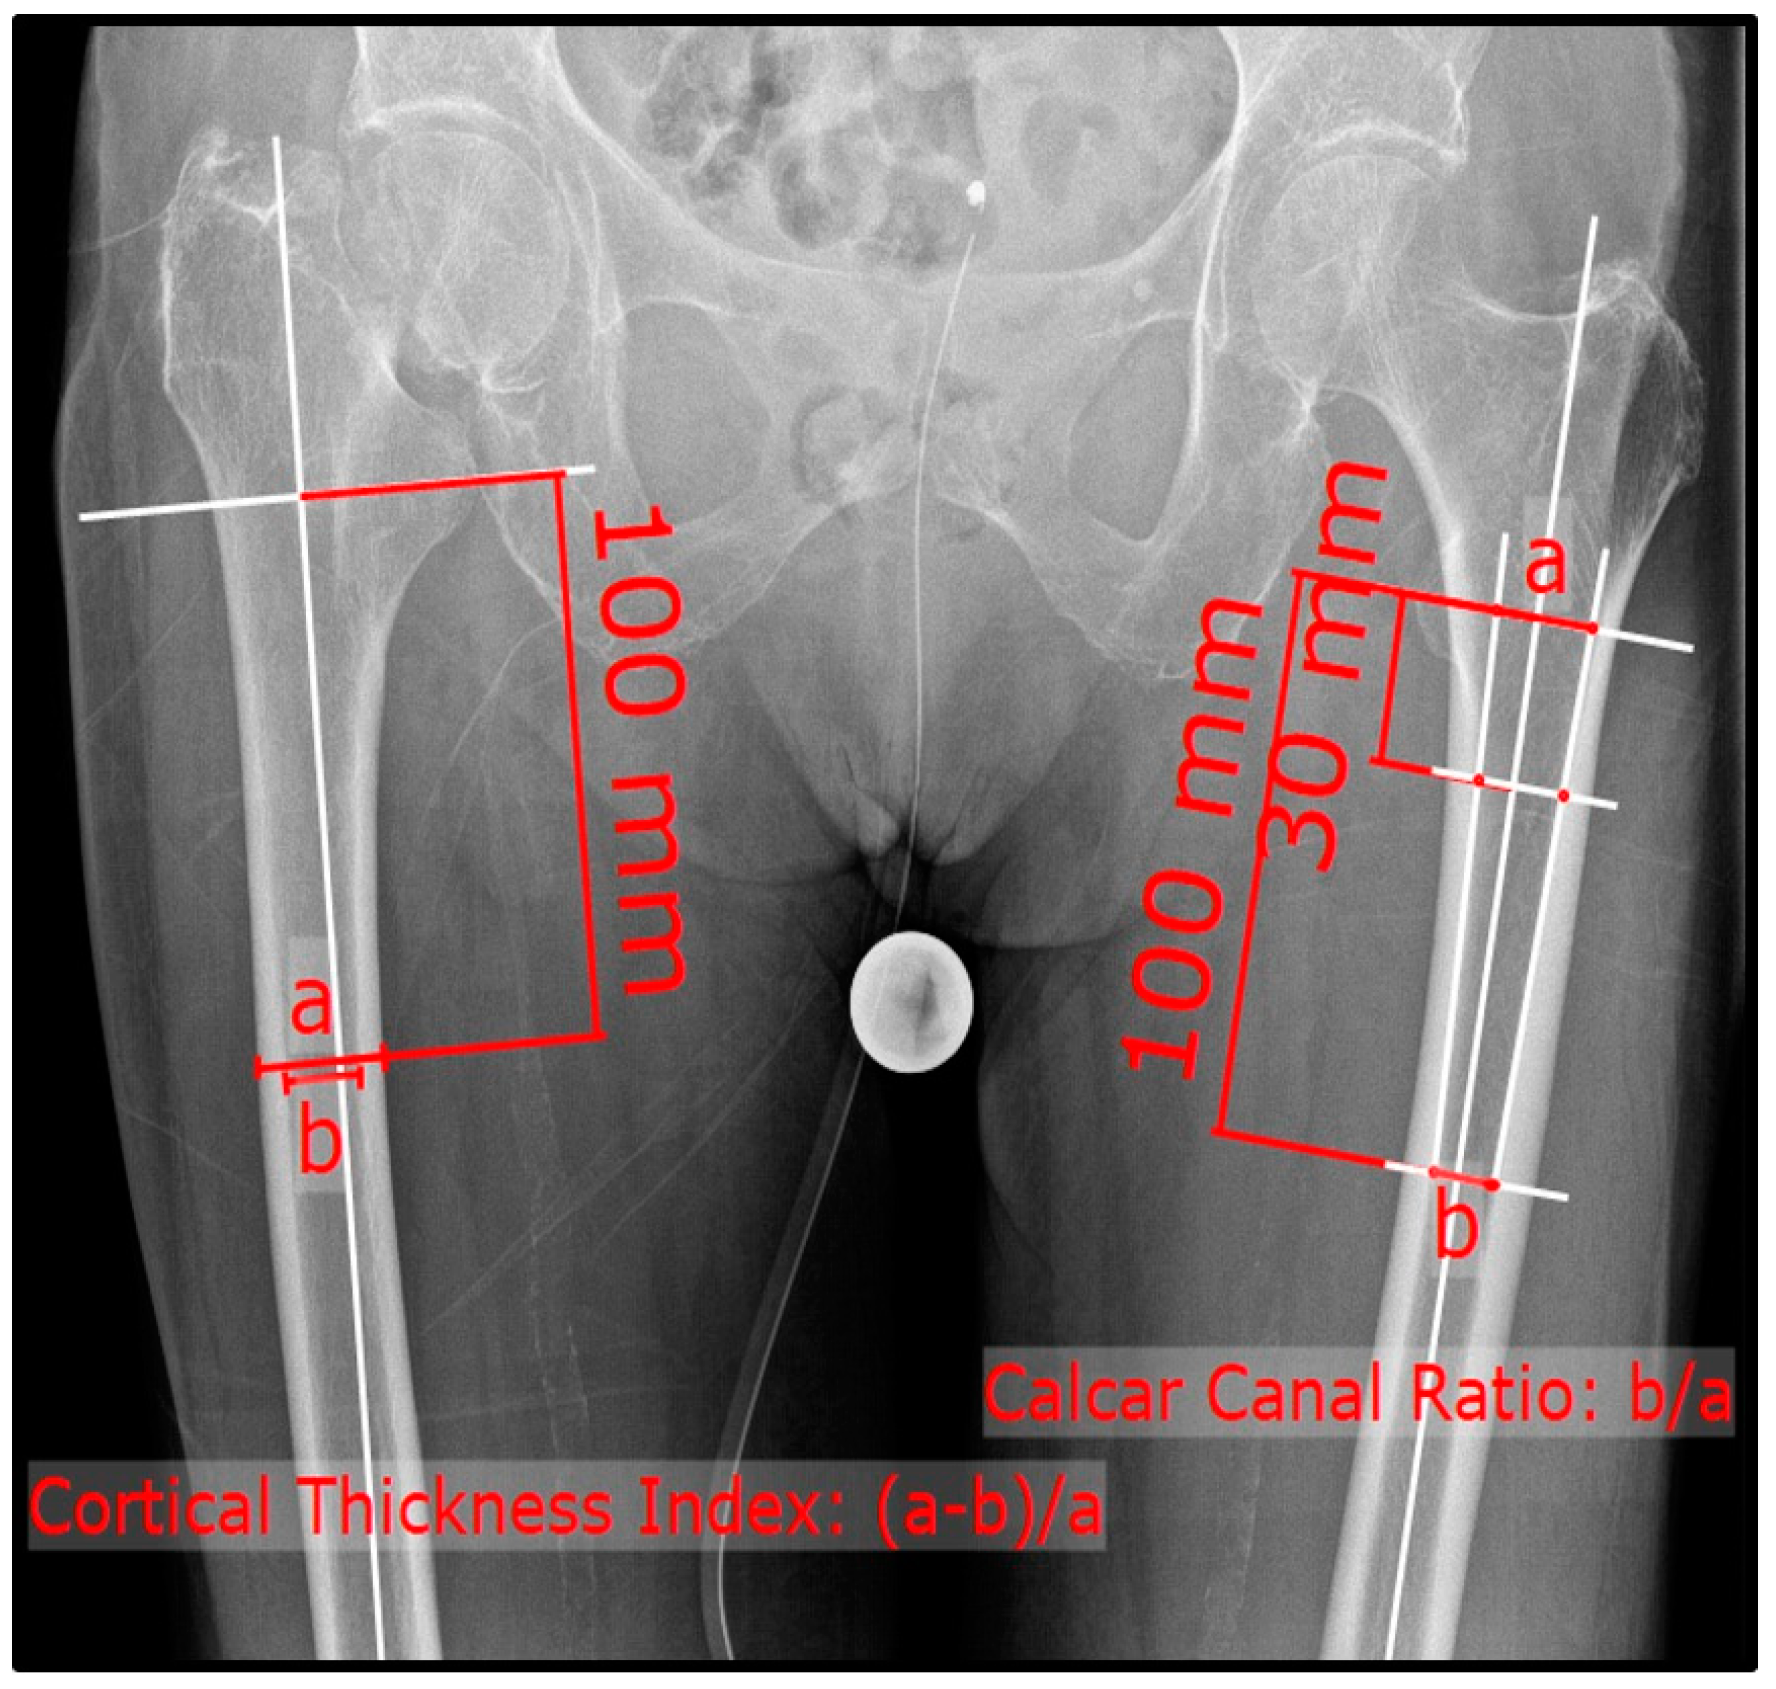

2. Materials and Methods

3.3. Comparison of CTI and CCR within the Sub-Groups

3.5. Correlations between CTI and CCR within the Sub-Groups